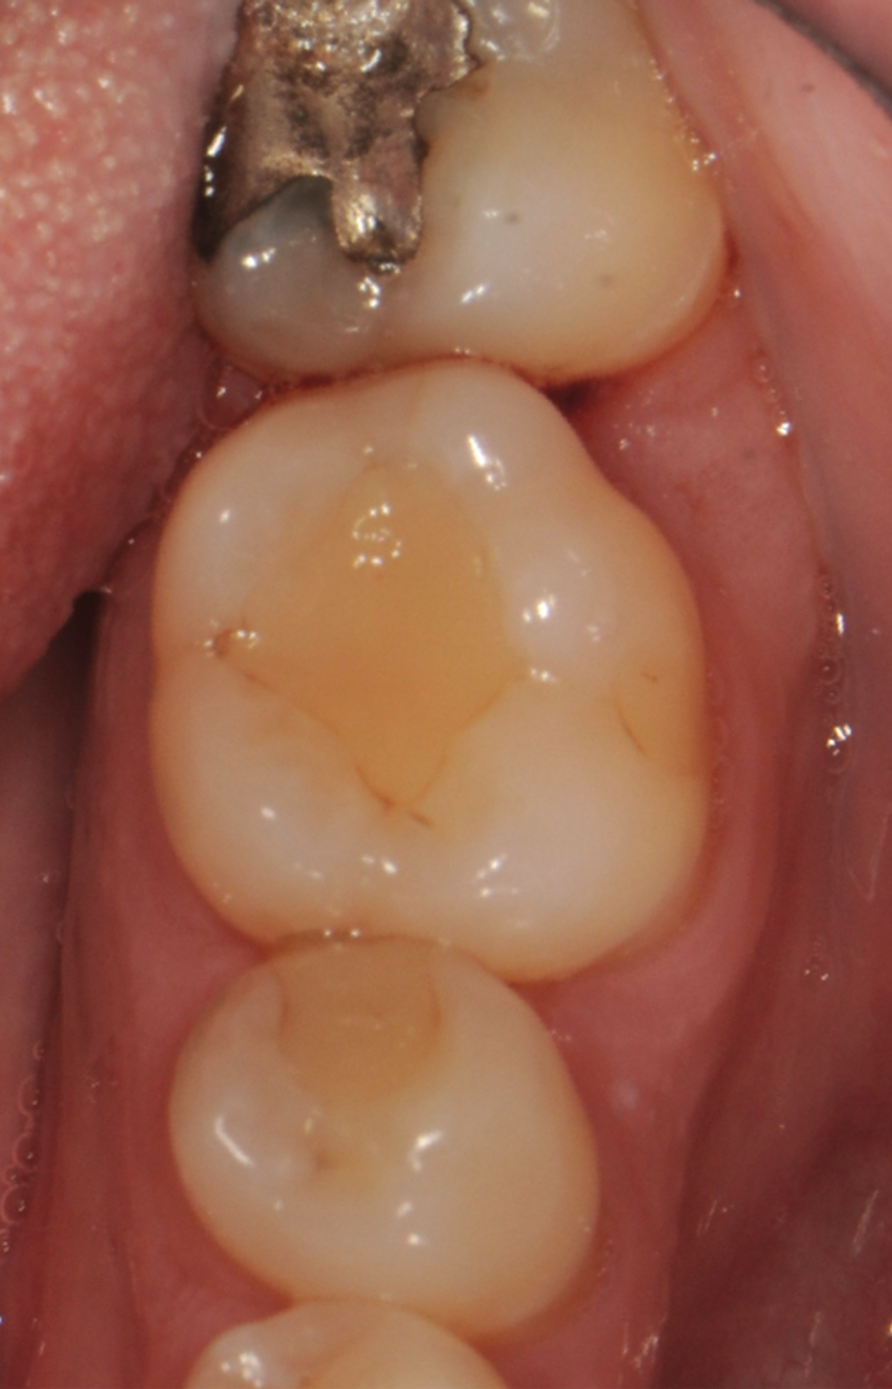

Fig 1. Tooth No. 19 at presentation, buccal view.

Figure 1

Fig 2. Tooth No. 19 at presentation, occlusal view. Note the thickness of the soft tissue and width of keratinized tissue.

Figure 2

In the case presented, a 56-year-old healthy nonsmoking male patient, diagnosed with periodontitis stage III, localized, grade B, had been under care in a private practice periodontal office (RAL) for 25 years. He had a history of good compliance with his treatment (full-mouth plaque score <20%). During the COVID-19 pandemic, the patient missed three supportive periodontal therapy (SPT) visits over a year, resulting in periodontal breakdown interproximal between teeth Nos. 18 and 19 (mandibular left second and first molars, respectively). At his most recent periodontal maintenance visit, significantly increased periodontal probing depths of up to 10 mm with bleeding on probing were noted (Figure 1 through Figure 3). The periapical radiograph revealed a deep, narrow three-wall intrabony defect at the distal aspect of tooth No. 19, with class I buccal furcation involvement (Figure 4). According to the periodontal risk score (PRS),15 formerly known as the Miller-McEntire periodontal prognosis index, the tooth prognosis at the patient's initial examination was "good" (score = 5), taking into account that he was unaware of his hemoglobin A1C (HbA1c) levels. This scoring motivated the patient to be tested, and his follow-up HbA1c was <6%, thus reducing his PRS to 3, which was considered "excellent," as the PRS target goal for regenerative procedures is a score of <5.15

Tooth No. 19 presented with no mobility and tested vital endodontically. Soft-tissue anatomy was intact, with a keratinized tissue width of >2 mm. The operator was experienced, with no environmental stress and used checklists. Thus, based on the presurgical risk assessment, the patient presented a low-medium risk for periodontal regenerative therapy (Table 2).